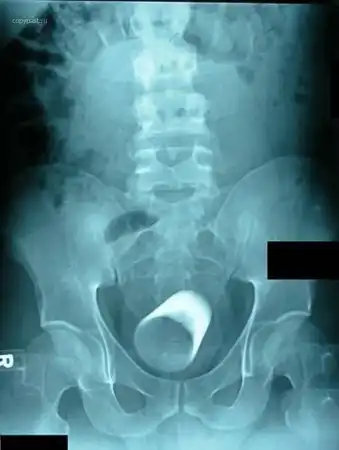

Стопка для шотов. В анусе. Зачем ее туда засунули? ))